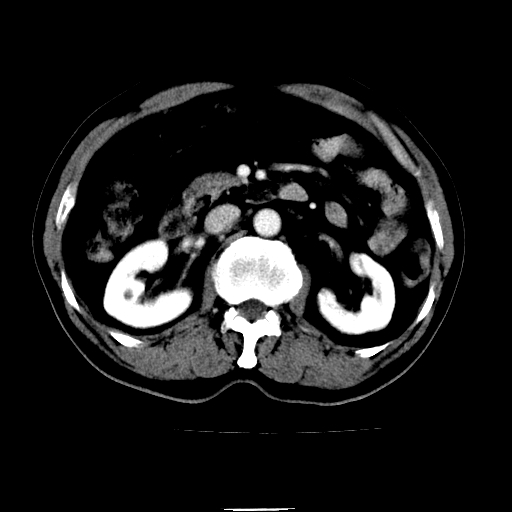

以下是引用chenqiong在2010-3-25 20:56:00的发言:[br]1、胆囊炎,胆囊息肉[br]2、肝内胆管及胆总管扩张,胆总管下端结石[br]3、十二指肠乳头旁憩室

以下是引用zxl51642在2010-3-26 10:47:00的发言:[br]胆囊炎,胆囊息肉,胆总管扩张,但未看到明显肿块,肝内胆管扩张不像恶性,炎性狭窄或阴性结石可能吧,建议mrcp,右肾小囊肿